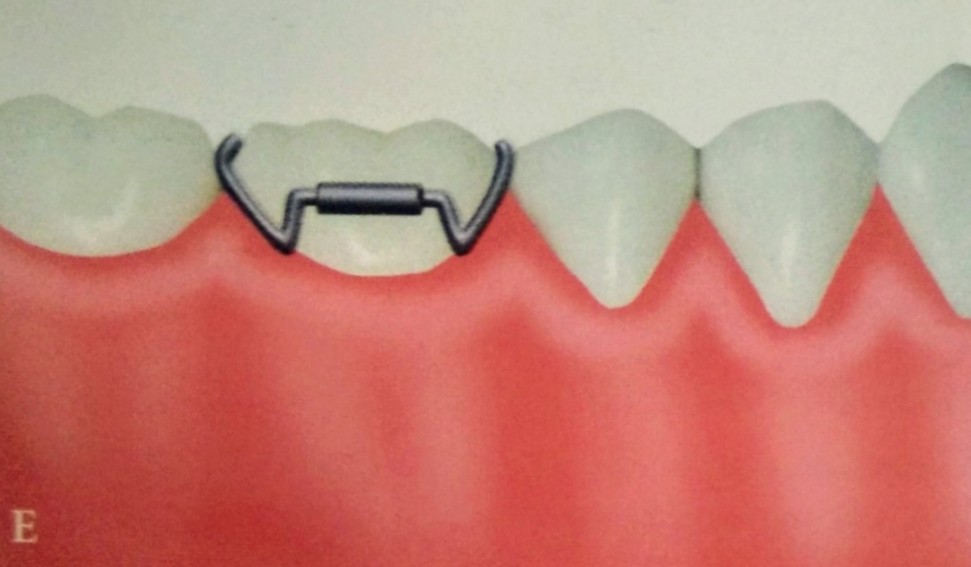

• The Adams clasp was first described by Professor Phillip Adams.

• It is also known as Liverpool clasp, universal clasp and modified arrowhead clasp.

• When properly constructed this clasp offers maximum retention.

• The clasp is constructed using 0.7mm hard round stainless steel wire.

The Adams clasp is made of the following parts:

a) Two arrowheads

b) Bridge

c) Two retentive arms.

The two arrowheads engage the mesial and the distal proximal undercuts.

The arrow head are connected to each other by a bridge that is at 45° to the long axis of the tooth.